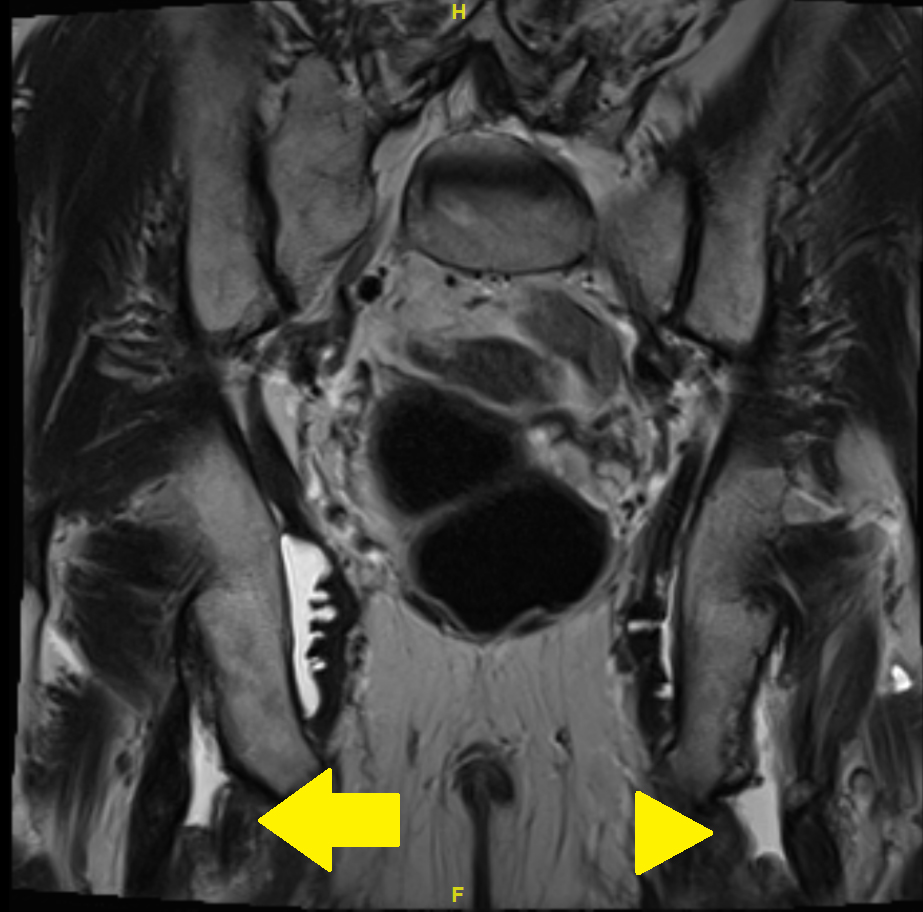

Because of a nonresponse to these measures, magnetic resonance imaging (MRI) of the pelvis was carried out. The MRI showed complete bilateral avulsion of the proximal hamstring muscles with the exception of some remaining fibres of the long head of the biceps femoris muscle on the right side (figs 1—4). There were no clear signs of inflammation nor any signs of myxoid degeneration. Also, there were no signs of inflammation in the area of the hamstring tendons in a past positron emission tomography-computed tomography (PET-CT) performed for melanoma follow up 4 months prior to the MRI.

Figure 1 MRI of the pelvis with T2 turbo spin echo (TSE) weighted image: coronary view. Arrow: partial avulsion on the right side; arrowhead: complete avulsion on the left side.